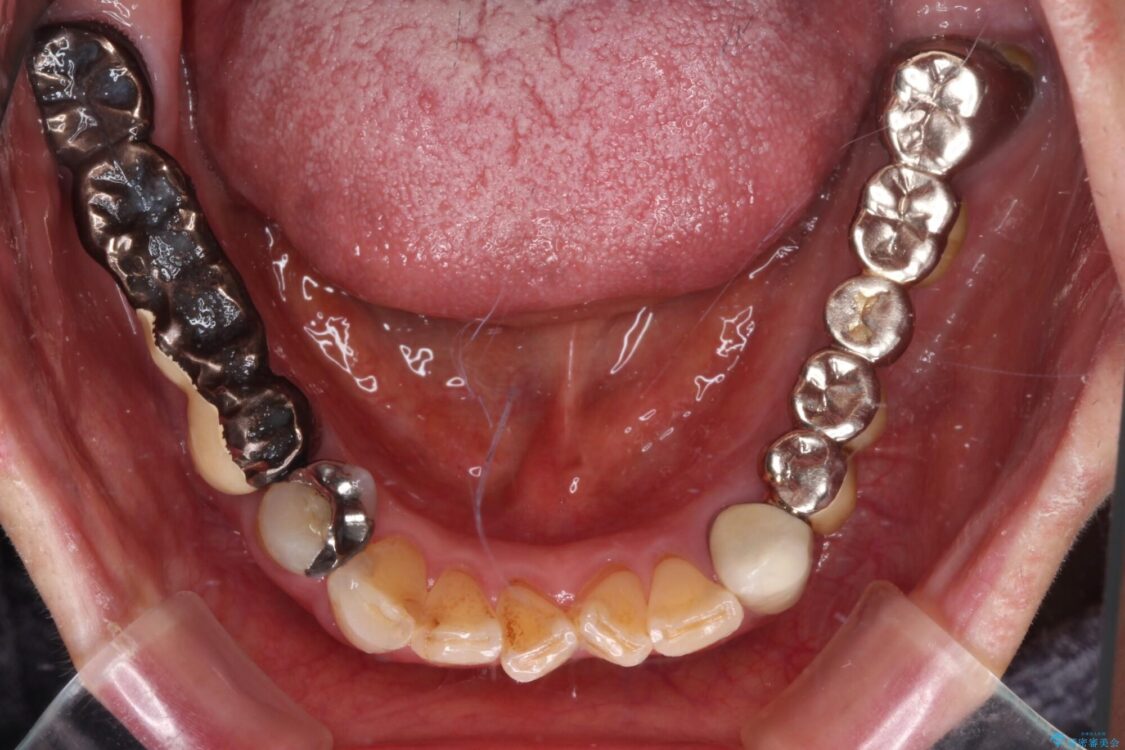

抜歯の必要な前歯や、以前治療した前歯のクラウンの外観を気にして来院された患者様です。

治療前

• 前歯をきれいにしたい インプラントや部分矯正を用いた総合歯科治療 治療前画像